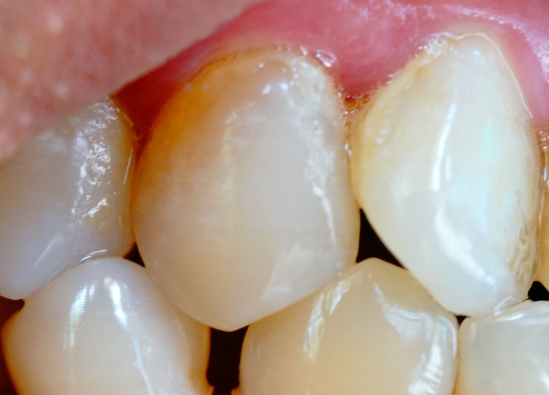

牙齒表面的牙釉質(zhì)掉了還可以修復(fù)嗎?

牙釉質(zhì)一旦掉了(即發(fā)生實質(zhì)性缺損)是無法再生的,因為牙釉質(zhì)是人體中唯一沒有細胞、沒有血管、不能自我修復(fù)的硬組織。但“不能再生”不等于“不能修復(fù)”——現(xiàn)代牙科有多種有效方法可以功能性或美觀性地修復(fù)牙釉質(zhì)…